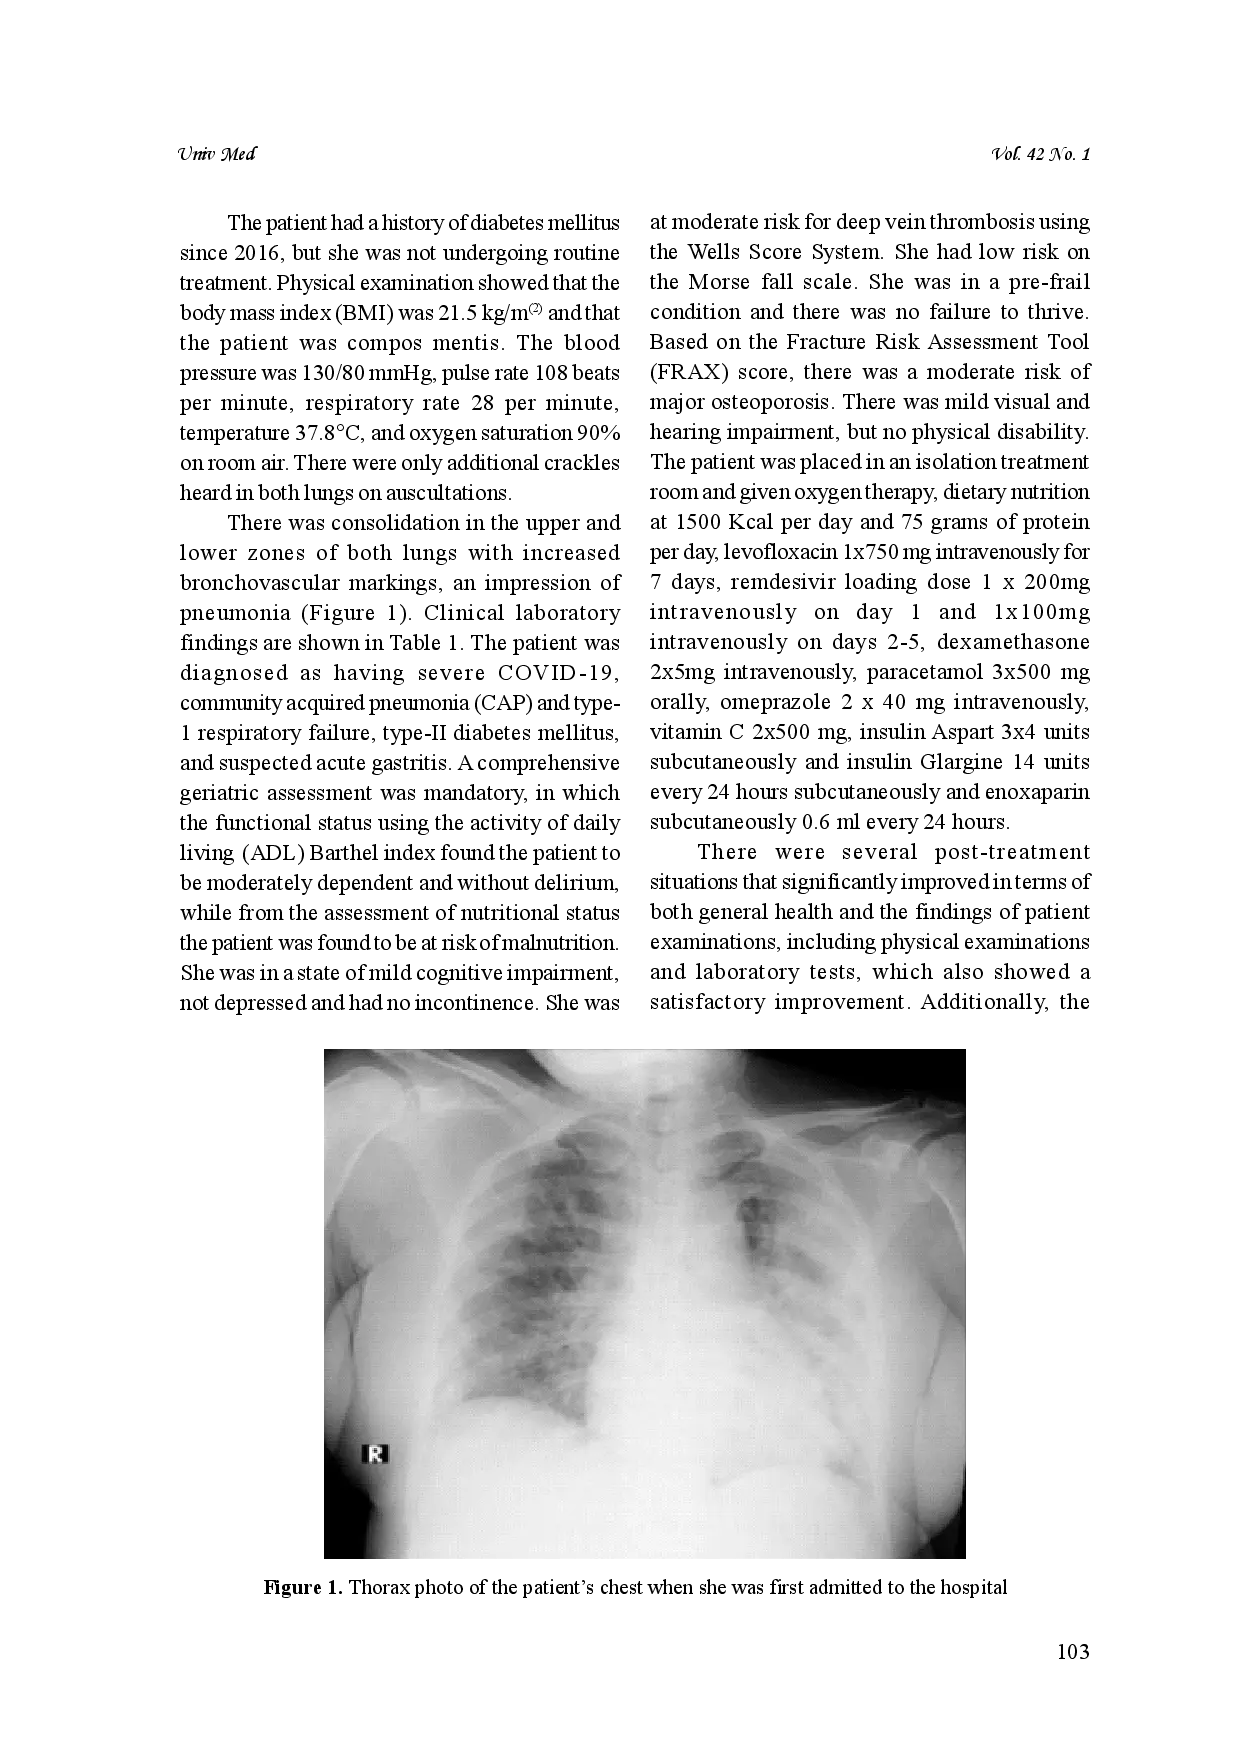

Infeksi COVID-19 pada lansia memiliki tingkat keparahan yang lebih tinggi, dikarenakan penurunan fungsi sistem kekebalan yang terkait dengan penuaan.Diperlukan pendekatan komprehensif dalam mengelola kasus COVID-19 pada lansia, termasuk penanganan komorbiditas dan kondisi geraik mereka.